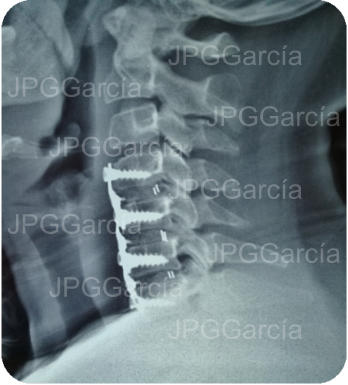

Extrusión discal cervical y tratamiento microquirúrgico

con colocación de cajas intersomáticas

Tratamiento neuroquirúrgico con colocación de cajas intersomáticas

cervicales hasta 3 niveles por vía anterior vistas anteroposterior y lateral

Tratamiento neuroquirúrgico

con colocación de cajas

intersomáticas cervicales hasta

3 niveles por vía anterior vistas

anteroposterior y lateral